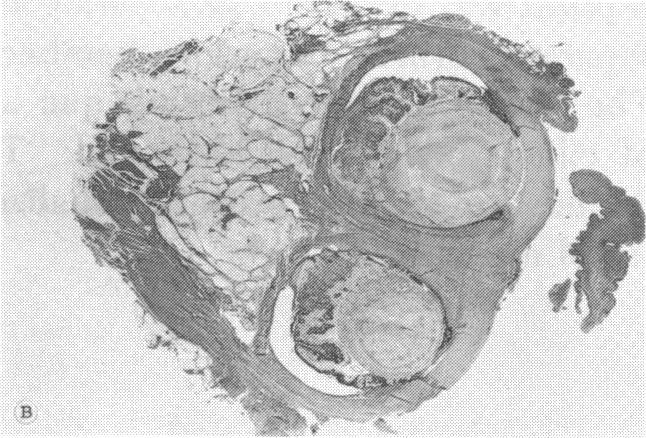

At the present time, essentially all known facts concerning cyclopia are consistent with some chromosomal disease, including clinical features of the pregnancy (fetal wastage, prematurity, intrauterine growth retardation, maternal age factor, complications of pregnancy), the generalized developmental abnormalities, specific ocular dysgenesis, by the high incidence of chromosomal abnormality already demonstrated, and the possibility of error in those cases of cyclopia with normal chromosomes. Even if chromosomal aberrations represent only one group of several different etiologic factors leading to cyclopia, at the present time chromosomal errors would seem to be the most common cause of cyclopia now recognized. Further studies will establish or disprove a chromosomal error in those instances which are now considered to be the result of an environmental factor alone or those with apparent familial patterns of inheritance. This apparent diverse origin of cyclopia can be clarified if future cyclopic specimens are carefully investigated. The evaluation should include a careful gross and microscopic examination of all organs, including the eye, and chromosome banding studies of all organs, including the eye, and chromosome banding studies of at least two cyclopic tissues. Then the presence or absence of multiple causative factors can be better evaluated.

目前,基本上所有关于独眼畸形的已知事实都与某些染色体疾病相符,包括妊娠的临床特征(胎儿死亡、早产、宫内生长迟缓、母亲年龄因素、妊娠并发症)、全身性发育异常、特定的眼发育不全,以及已证实的染色体异常的高发生率,还有那些染色体正常的独眼畸形病例存在错误的可能性。即使染色体畸变只是导致独眼畸形的几种不同病因中的一组,目前染色体错误似乎是现在所认识到的独眼畸形最常见的原因。进一步的研究将证实或否定那些目前被认为仅由环境因素导致或具有明显家族遗传模式的病例中的染色体错误。如果对未来的独眼畸形标本进行仔细研究,这种明显多样的独眼畸形起源可能会得到阐明。评估应包括对所有器官,包括眼睛,进行仔细的大体和显微镜检查,以及对所有器官,包括眼睛,进行染色体显带研究,并且至少对两个独眼畸形组织进行染色体显带研究。这样就能更好地评估多种致病因素的存在与否。